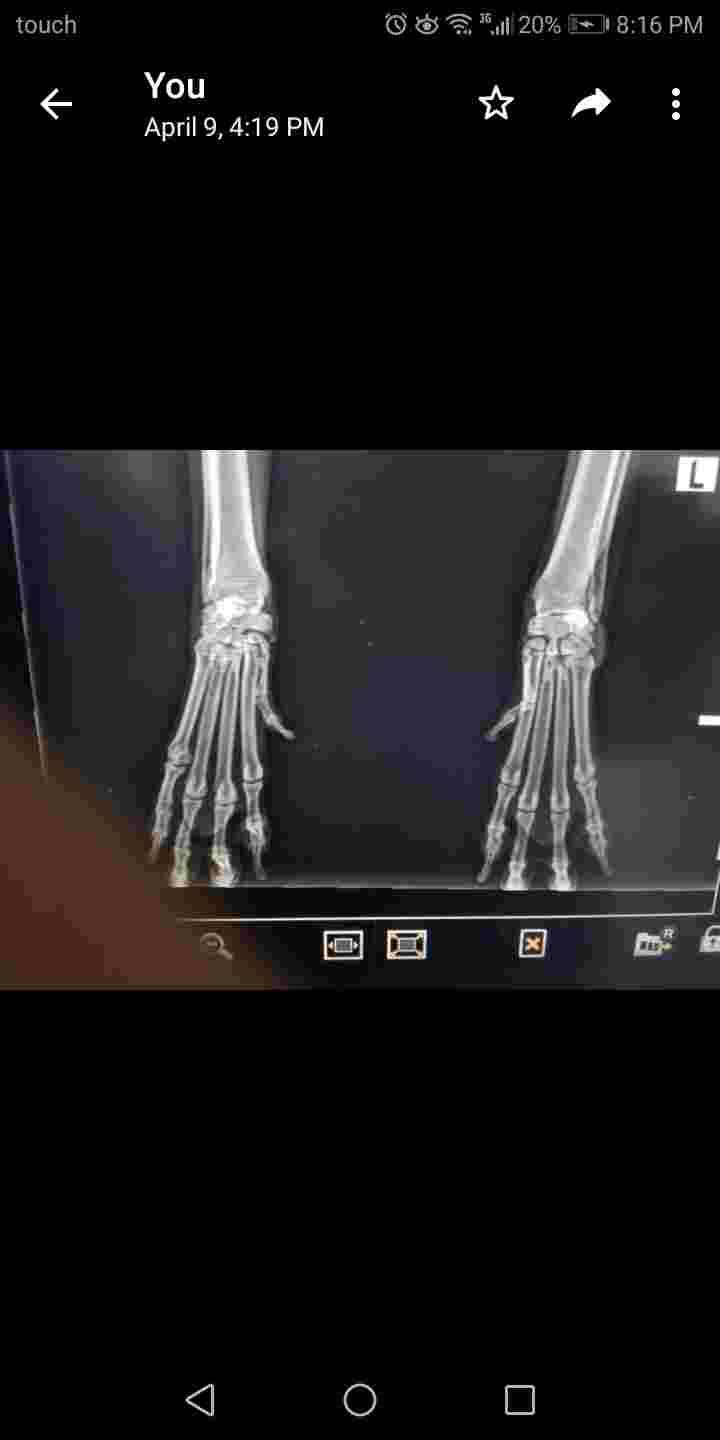

Hi Dr. Can you please check xray of my femele 10yrs golden. She is on glucosamine since a year now she sometimes limps the vet said it's not dangerous but he didn't explain to me what should I give her supplements more or if the xray is not bad can you give me info I care for her health at this age.

Unfortunately its very hard to interpret pictures of X-rays that have been uploaded; detail and subtle changes are difficult to appreciate. Having said that, I don't see anything in these X-rays that is terribly concerning to me. It may be that she does have some arthritis pain causing her occasional limp. Glucosamine supplements can be helpful. Cosequin is a great one , so is Glycoflex. Physical therapy offered by a canine rehabilitation professional can be helpful for older dogs in terms of maintaining comfort, health, and mobility. Find someone here: https://www.rehabvets.org/directory.lasso Acupuncture can also be really helpful for these guys. Ask your vet if they do acupuncture, or if they recommend anyone in particular. If not, find a veterinary acupuncturist here: https://curacore.org/find-a-practitioner/ I hope that helps! Thanks for asking PetCoach!